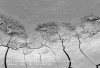

Figure 5  Irregular contour of CEJ showing aggregations of biofilm in scalloped enamel recesses (arrows). Enamel is at top and cementum at bottom of photograph. Cracks in cementum are the result of dehydration during specimen preparation. Bar = 100 µm at an original magnification of 300x.

Figure 5

Figure 6  High-magnification view of biofilm noted in Figure 5. Biofilm is dominated by long filamentous microbes and shows signs of mineralizing to become dental calculus (circle). Bar = 20 µm at an original magnification of 1,500x.

Figure 6